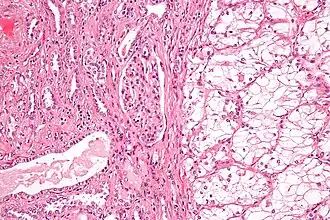

| Micrografia de tecido renal. À direita: carcinoma de células renais do subtipo de células claras, o subtipo mais comum. À esquerda: tecido normal sem cancro. | |